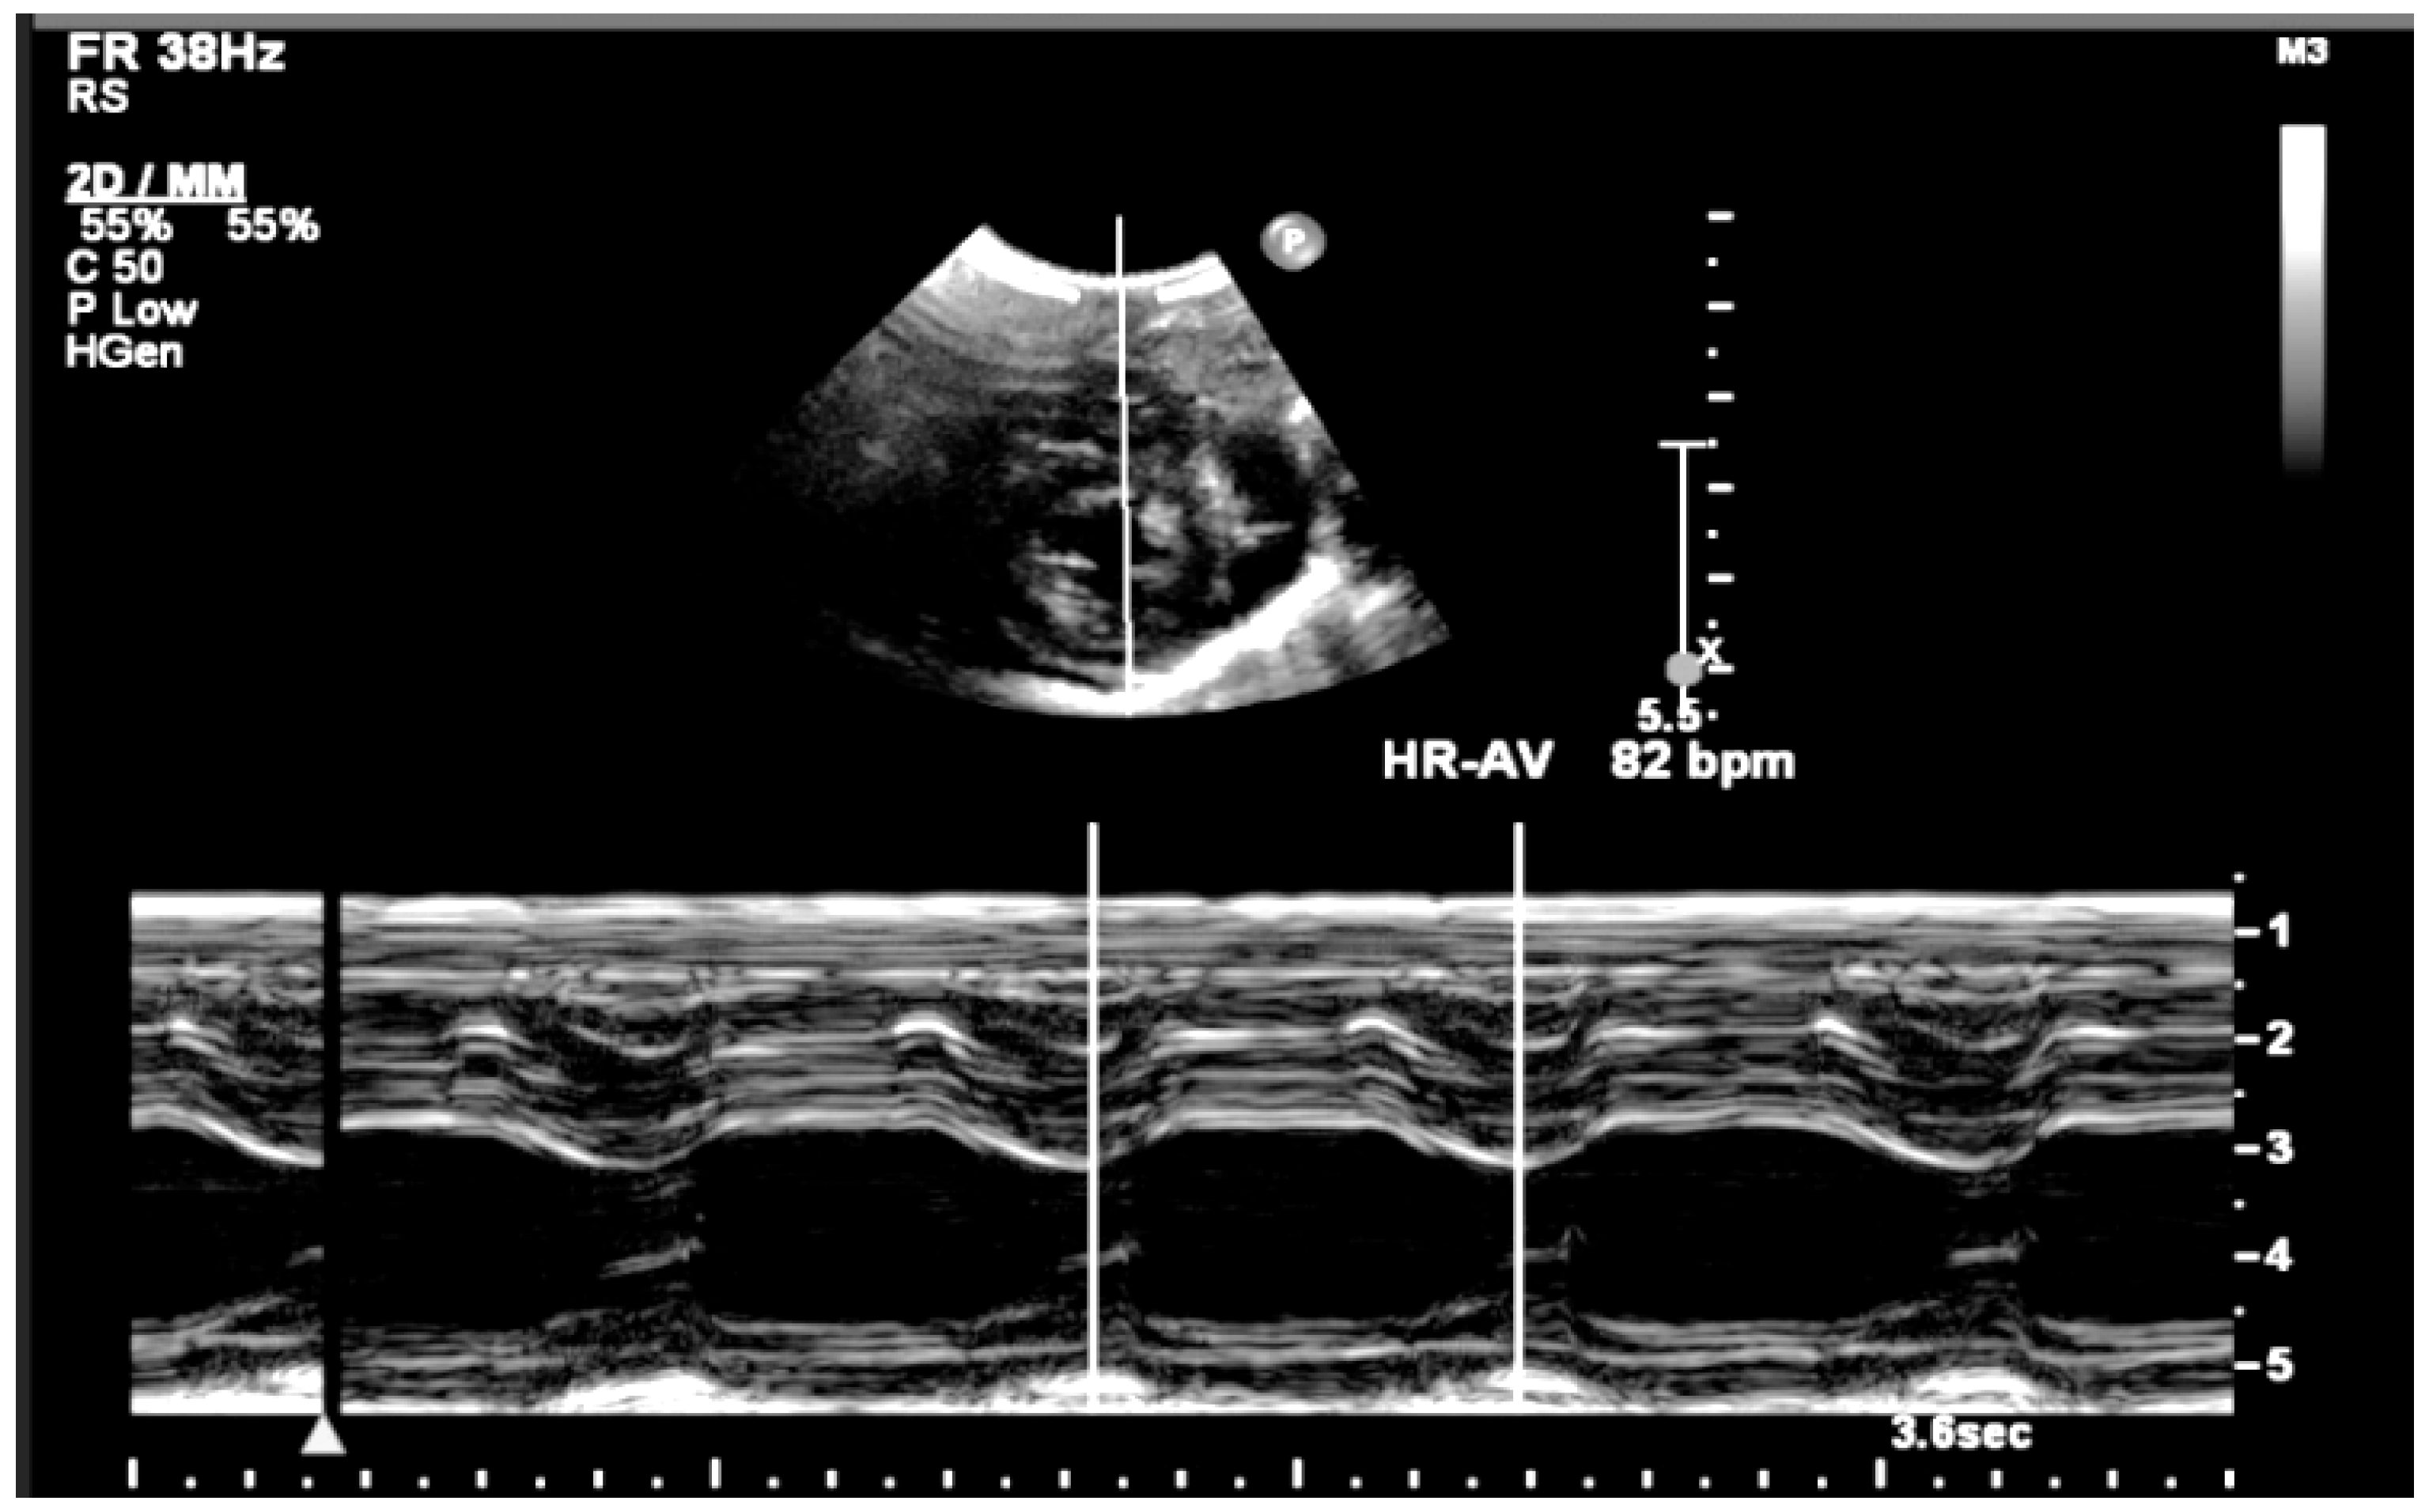

| 26 + 0 | Start of dexamethasone 4 mg/day | 60 | SF increased from 34% to 47%, but qualitative contractility decreased | Mild edema; no beta- agonists used |

| 28 + 0 | First IVIG cycle (65 g total) | 75 | SF increased to 52%; mild improvement in contractility | Initiated due to signs of fibroelastosis |

| 31 + 2 | Post-IVIG peak response | 70 | SF: 59% (LV), 52% (RV); marked biventricular improvement | Aortic isthmus 3 mm (Z-score –1.65) |

| 33 + 0 | Second IVIG cycle | 68 | Stable function maintained | Repeated full protocol; no complications |

| 36 + 3 | Delivery | 84 | – | Stable neonate; no pacemaker needed |